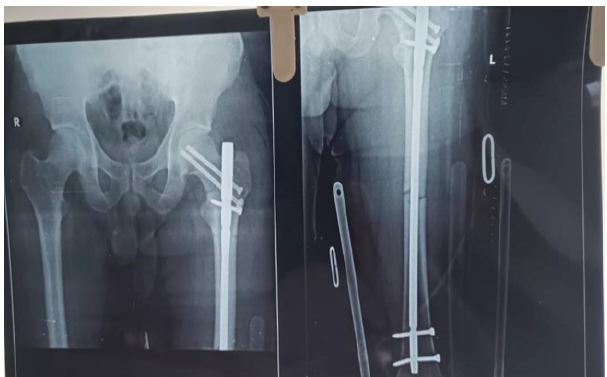

Patient was hemodynamically stable with Blood pressure of 130/80 mmhg and saturation of 97% on room air. Any other injury was ruled out and he was then admitted in Goa Medical College on June 17, 2025. Investigations revealed low hemoglobin of 9.2 g/dL; the rest of the investigations, including Renal and liver function tests, were normal. Computed tomography pulmonary angiography was done to rule out pulmonary embolism and was found to be normal. He was kept on 4L oxygen with a facemask and low molecular weight heparin till the operation. After omitting heparin 12 h before the surgery, the patient was then taken to OT on June 21, 2025 under combined epidural and spinal anesthesia. Two important things, which had to be addressed: First, to reduce distraction at the shaft fracture and second, the neck fracture. The patient was positioned on a traction table. The same incision was used. First, the femur nail tip was felt and identified and then the femur jig was connected to it. Then, both the proximal bolts were removed to backslap the nail till the fracture site gap of the shaft got reduced, and then only the proximal dynamic bolt was put. Now, for neck fracture, two 6.5 mm Cannulated Cancellous screws (one with a washer) were passed from the neck to the head of the femur. Both the screws have to be put in the posterior quadrant as the entry of the femur nail was found to be a little anterior. Good compression was achieved at both the fracture sites (Figs. 3 and 4).

Figure 3: Intraoperative C-arm shoots of hip anteroposterior and lateral views and the shaft anteroposterior view shows two cannulated cancellous screws for neck femur, screws are in the posterior quadrant, as nail entry was anterior fracture gap at shaft was reduced and only proximal dynamic bolt inserted.